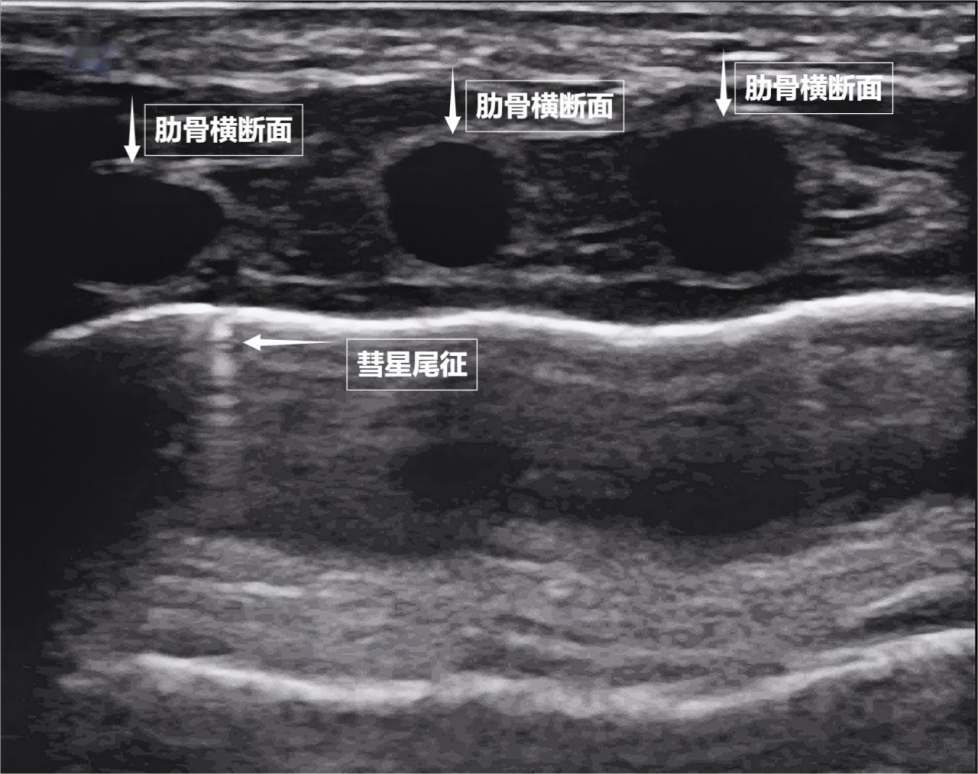

第二景:“沙滩与浪花”——肺滑动征

如果我们把超声图像调成实时动态模式,把“照片”变成“电影”,更神奇的一幕出现了。随着呼吸,胸膜线会随胸廓运动轻柔滑动,这就是“肺滑动征”。它意味着肺与胸壁正紧密相依、自由顺畅地呼吸。若肺与胸壁间有气胸或胸腔积液,这种滑动会消失。有时,在胸膜线下方还会出现细小的亮白色闪烁点,称为“彗星尾征”(见下图)。其少量、孤立出现时,通常是正常肺小叶间隔的反射,无需担心。

图为正常新生儿肺部超声表现